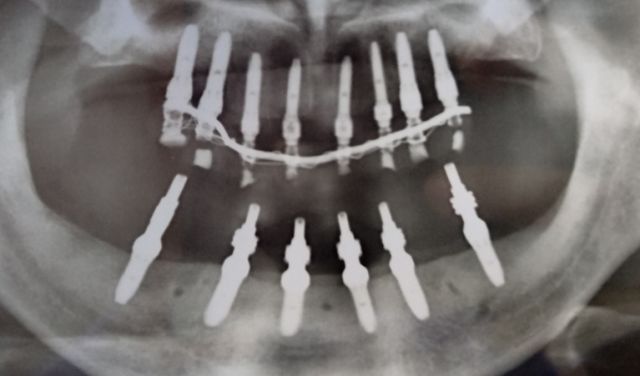

精彩案例: